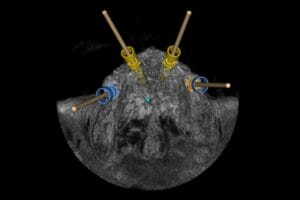

We use a CBCT (cone beam CT) scan alongside digital impressions and photography to create a precise 3D model of your mouth. This allows us to plan your implant placement virtually.

Step 3 – Digital planning

Using a 3D navigation system, our dentists position implants digitally at the perfect angle and depth. This plan is then transferred into a customised surgical guide and if needed temporary teeth, which can be placed directly onto the newly placed implants.

A dental navigation system is a computer-aided tool that guides dentists during implant placement. It merges CBCT scans with digital impressions to create a virtual 3D model of your mouth. The system then provides real-time guidance so the implant is positioned at the exact angle, depth, and location planned in advance. This improves accuracy, reduces invasiveness, and ensures long-lasting results compared with freehand placement.